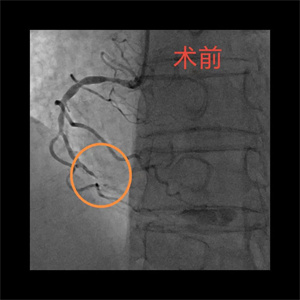

患者,李大爷(化名),76岁,因突发胸痛被家属送至我院急诊科,经完善心电图等检查后,被诊断为急性心肌梗死,随后,病人迅速被送至导管室。完善冠脉造影检查后,患者血管显影结果不容乐观,考虑左主干真性分叉合并三支病变,即右冠慢性闭塞、回旋支急性闭塞、前降支严重狭窄伴钙化。与此同时,患者出现血压、氧饱和度下降的情况,病情极其危重,随时面临死亡风险,已无法耐受及等待外科搭桥手术,急需急诊介入治疗。

关键时刻,心血管内科副主任医师吴义权、主治医师孙春根、夏秋旺和介入团队紧密协作,在IABP的保护下快速开通血管。术后,患者转入心血管内科监护病房。在医护团队的精心医治和悉心照料下,现已平安出院。